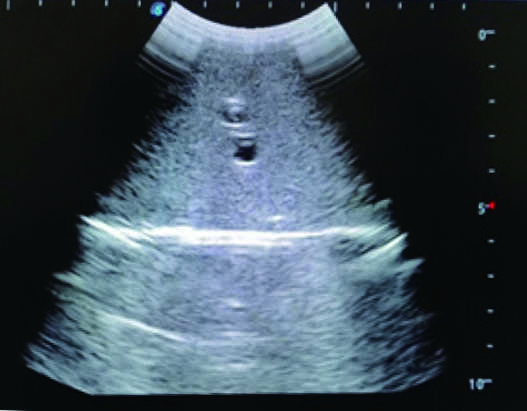

2) Real clinical ultrasound images with clear anatomical structures like intestines, part of the liver, arteries and veins, etc.

1) Ultrasound-guided puncture and abdominocentesis practice